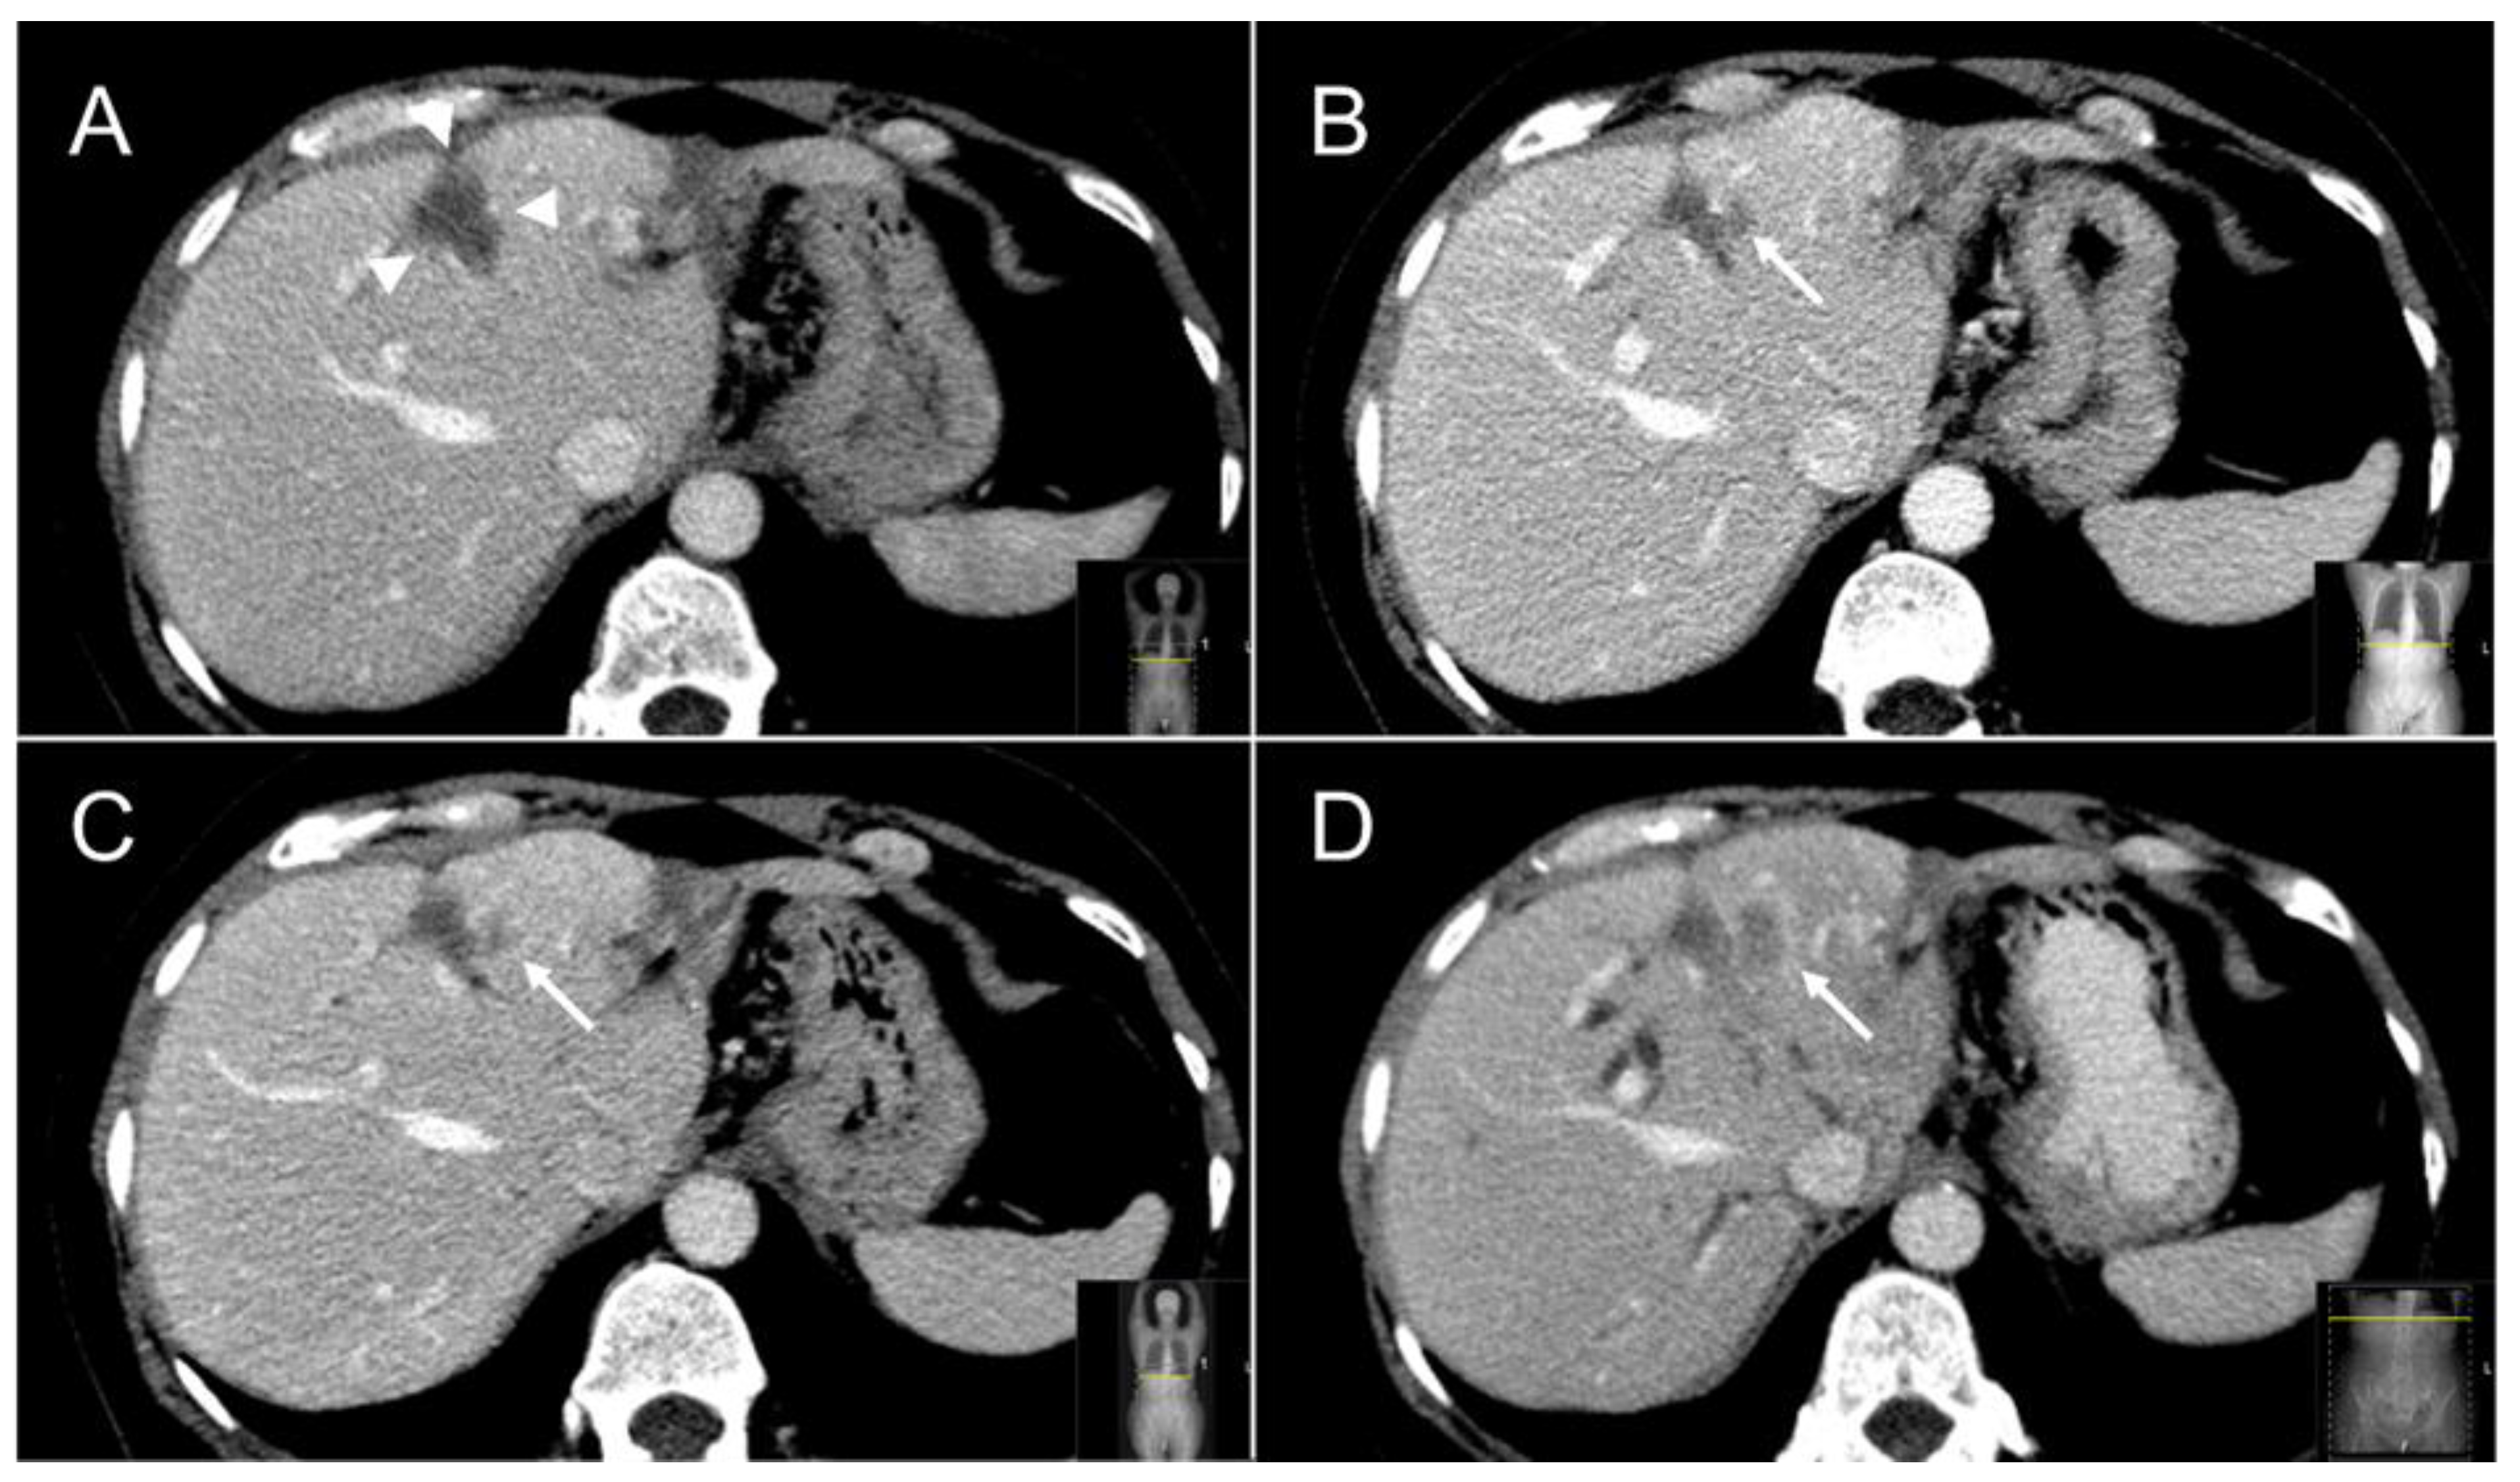

2.5. Follow-Up

- Tetreau, R.; Llacer, C.; Riou, O.; Deshayes, E. Evaluation of response after SBRT for liver tumors. Reports of practical oncology and radiotherapy. J. Greatpoland Cancer Cent. Pozn. Pol. Soc. Radiat. Oncol. 2017, 22, 170–175. [Google Scholar]

- Jarraya, H.; Borde, P.; Mirabel, X.; Ernst, O.; Boulanger, T.; Lartigau, E.; Ceugnart, L.; Kramar, A.; Taieb, S. Lobulated Enhancement Evaluation in the Follow-Up of Liver Metastases Treated by Stereotactic Body Radiation Therapy. Int. J. Radiat. Oncol. 2015, 92, 292–298. [Google Scholar] [CrossRef] [PubMed] [Green Version]

- Yip, C.; Cook, G.J.R.; Owczarczyk, K.; Goh, V. Challenges in imaging assessment following liver stereotactic body radiotherapy: Pitfalls to avoid in clinical practice. Chin. Clin Oncol. 2017, 6 (Suppl. 2), S11. [Google Scholar] [CrossRef] [PubMed] [Green Version]